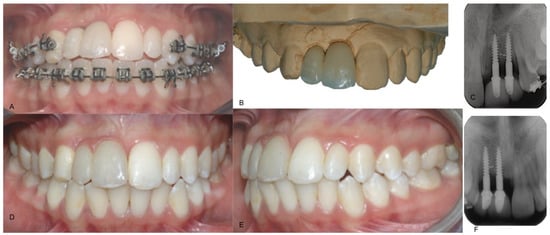

A male patient, currently 27 years old, was seen for a consultation at the age of 13, fourteen days after a basketball game traumatic injury. The patient presented with an intrusive dislocation of the upper central and lateral incisor (#11, 12) which had been repositioned, treated endodontically and splinted with a multi-bracket orthodontic during an emergency visit. After some healing time, the splint was removed and upon clinical and radiographic evaluation, the failure of the reimplantation was noticeable (Figure 1).

Figure 1. Intraoral pretreatment photographs and radiographs illustrating preoperative (A) buccal clinical view of anterior teeth, (B) occlusal clinical view of anterior teeth and (C) periapical X-ray.